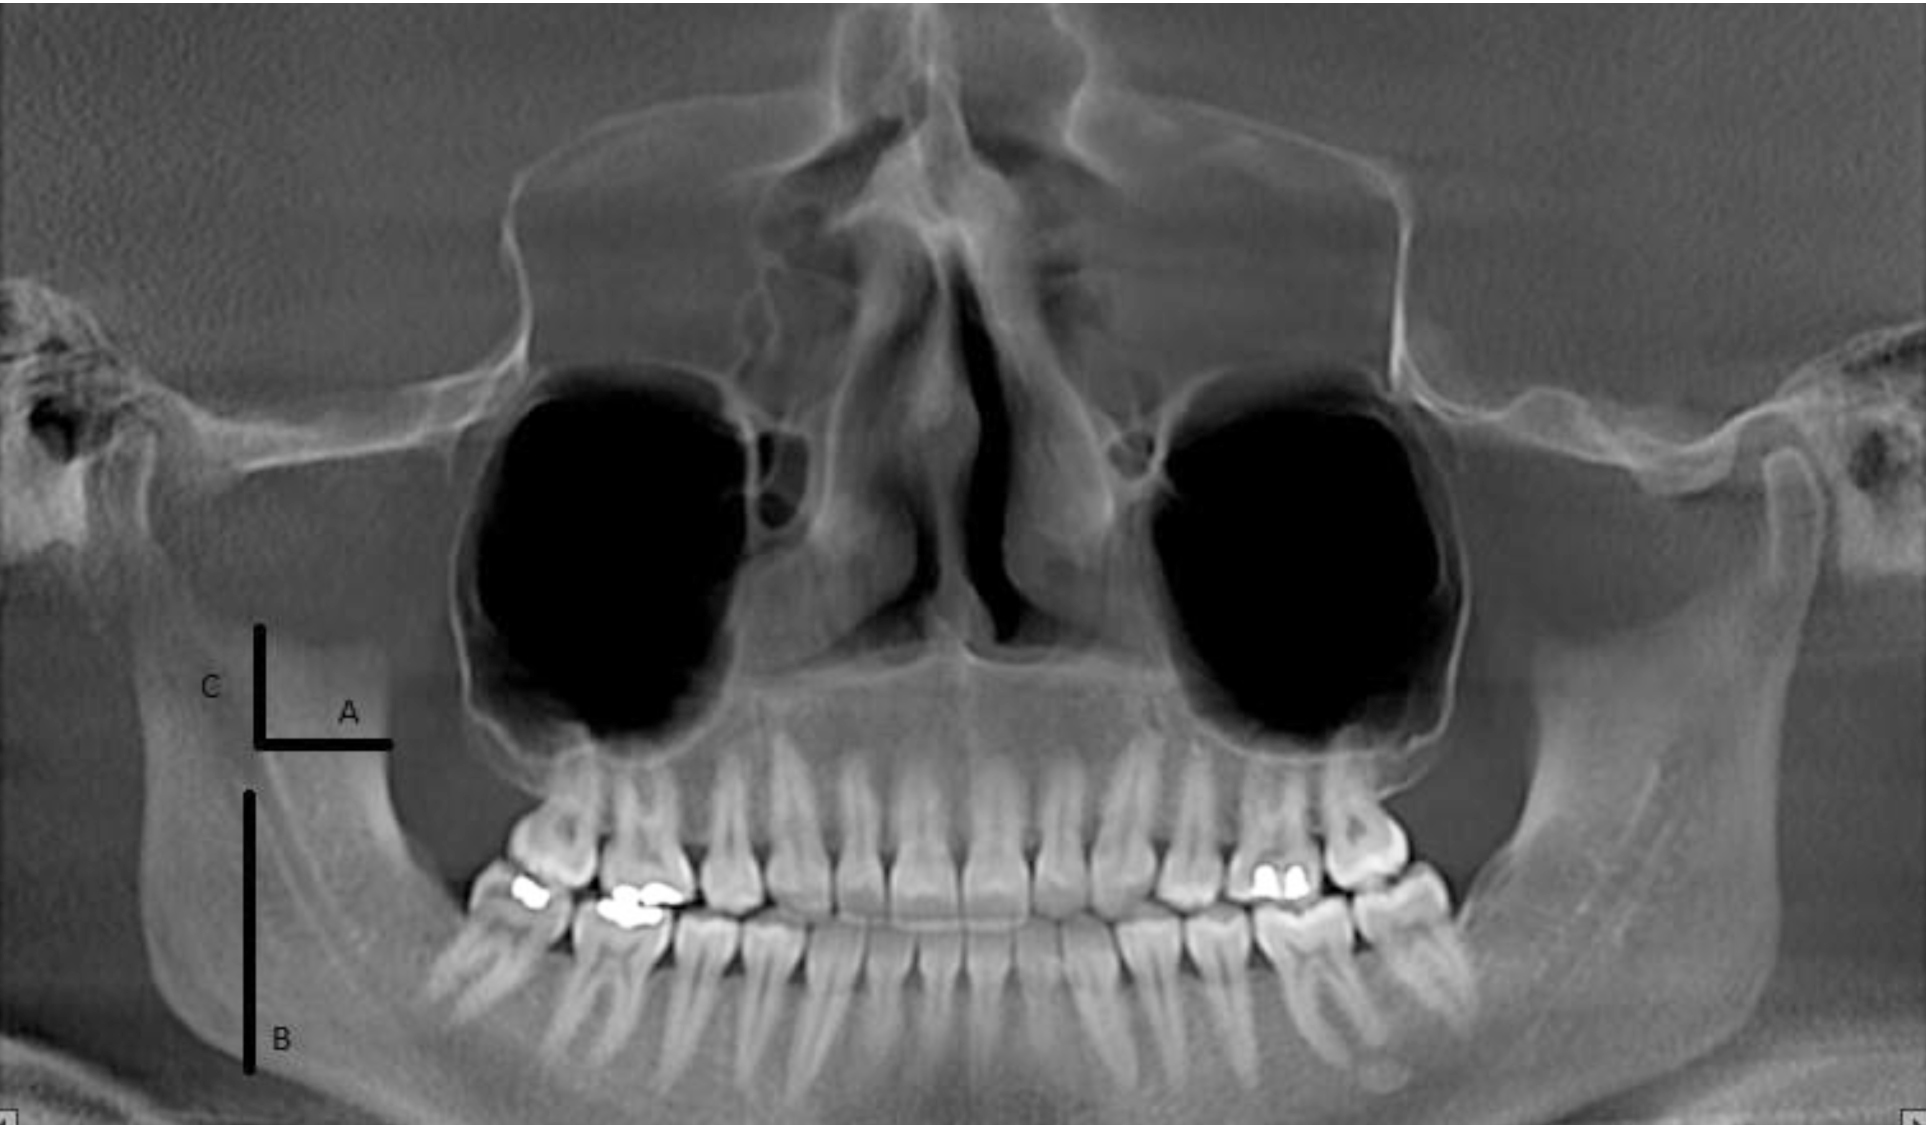

To determine the position of MF in the mandibular ramus, four distances were measured on CBCT images in NNT Viewer software and reported in millimeters. The distances and their definitions were as follows (Figure 1):

Distance A: Distance (Mean±SD) between the anterior border of MF and the cortex of the anterior border of mandibular ramus.

Distance B: Distance (Mean±SD) between the inferior border of MF and cortex of the inferior border of mandibular ramus.

Distance C: Distance (Mean±SD) between the superior border of MF and cortex of the superior border of mandibular ramus.

Figure 1. Measurement of A, B and C distances on CBCT scans to determine the position of mandibular foramen.